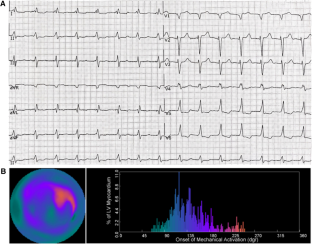

Ninety-six AHF patients who received standard 12-lead ECG, gated single-photon emission computed tomography (SPECT) myocardial perfusion imaging (MPI), and echocardiography were enrolled. Thirty-two normal subjects were collected as the control group to get the normal database of mechanical dyssynchrony. The end point is the composite of all-cause death and heart transplantation. Electrical dyssynchrony was defined as QRS duration > 120 ms. Mechanical dyssynchrony was defined as > mean + 2 × SD phase standard deviation (PSD) or phase bandwidth (PBW) based on our normal database.

During the follow-up of 28 ± 10 months, complete data were obtained in 92 patients. 26 (28.3%) Patients who reached the end point were classified into the event group. There were no significant differences in PSD or PBW between the event and non-event groups. However, PBW > 77.76° was independently associated with the end point in the univariate and multivariate analysis (hazard ratio 2.92, 95% confidence interval 1.00-8.47, P = .049; hazard ratio 3.89, 95% confidence interval 1.01-14.97, P = .048). The Kaplan-Meier curve with a log-rank test showed that the end point rate was significantly higher in the patients with PBW > 77.76° (log-rank P = .039). Moreover, the ROC curve analysis showed that the area under the curve (AUC) for predicting end point events by the integrative analysis of QRS > 120 ms and PBW > 77.76° was significantly improved compared to QRS duration > 120 ms (AUC: 0.75 vs 0.68, P = .001) or PBW > 77.76° (AUC: 0.75 vs 0.62, P = .049), respectively. The model of combined electrical and mechanical dyssynchrony yielded a further significantly improved risk prediction for adverse events in the global χ2.

The combination of QRS duration > 120 ms and PBW > 77.76° was an independent predictor of all-cause death and heart transplantation in AHF patients. The integrative analysis of electrical and mechanical dyssynchrony provides incremental prognostic value for clinical use.